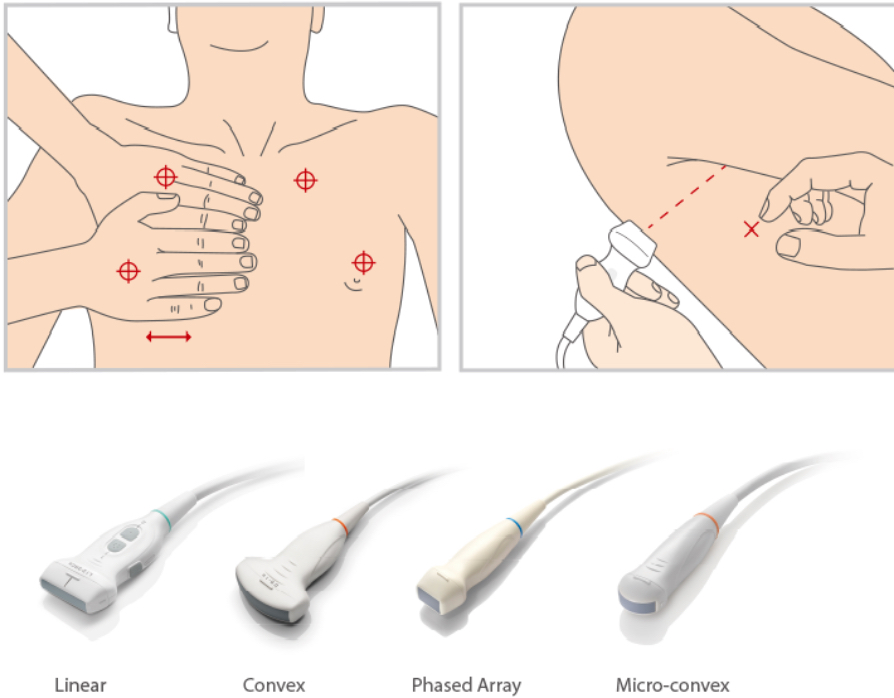

How to Scan?

Ultrasound Performance